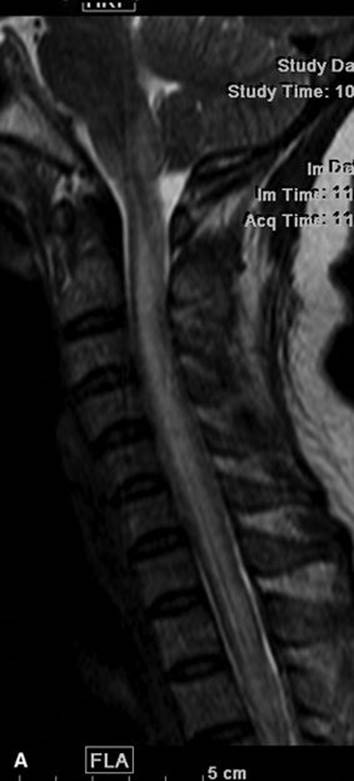

C. Cervical spine injury. Plain X-rays remain the first-line imaging method in patients with cervical spine trauma and should include at least anteroposterior, lateral, and open-mouth (odontoid) views. Cervical spine CT offers submillimeter resolution allowing the detection of subtle fractures not seen on plain films. MRI is used to evaluate for spinal cord injury, which appears bright on T2 pulse sequences and dark on gradient echo sequences because of the magnetic susceptibility effect of acute blood.

Cervical spondylosis is the most common cause of neck pain and cervical radiculopathy, and its incidence increases with age. It is characterized by hypertrophic arthropathy of the facet joints, osteophyte formation at the disk margins, and progressive intervertebral disk degeneration and herniation. All these changes result in central canal and neural foraminal stenoses, with resulting restriction of the spinal cord and the nerve roots. In younger patients, sudden disc herniation may cause acute symptoms. Other causes of cervical pain and radiculopathy include syringomyelia with or without Chiari’s malformation, benign tumors of the spinal canal or the neural foramina like schwannomas and meningiomas, demyelinating disease, and post-traumatic myelomalacia. MRI is the preferred method to image these patients because it allows superior evaluation of the cervicomedullary junction, the cord, the spinal canal, and the neural foramina. CT myelography may be useful in patients with cervical spondylosis and contraindications or intolerance to MRI (Fig. 32.8A and B).

FIGURE 32.8 T2 sagittal image (A) and axial image (B) demonstrate a large left paracentral disc protrusion at the C5-6 level with marked deformity of the underlying cord with increased signal in the cord that may represent edema or myelomalacia.